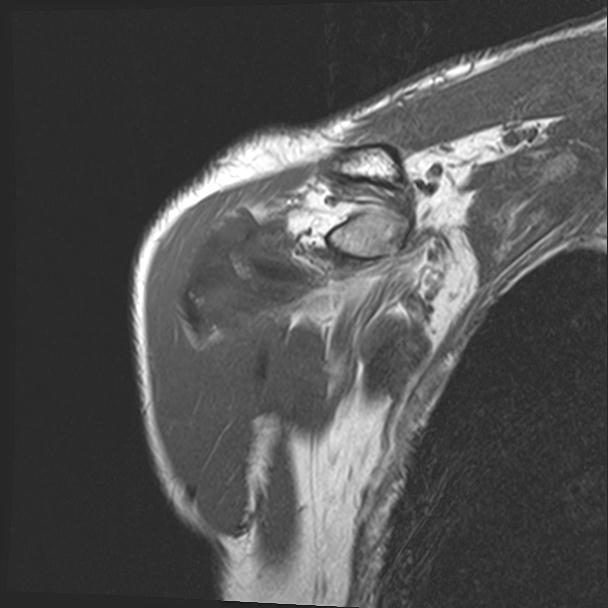

60058 3/9 11/4 右肩 2R+MRI 73歳男性 肩腱板損傷